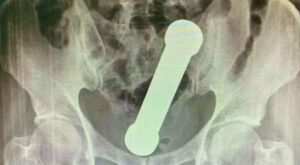

La víctima, de 54 años, se presentó en un hospital de la ciudad Manaos, noroeste de Brasil, con dolor abdominal, náuseas y dificultad para defecar. Le hicieron una radiografía que mostró que tenía un objeto de metal de 4,4 libras y casi 20 cm en el ano. Se calcula que la mancuerna estuvo alojada allí por lo menos dos días.